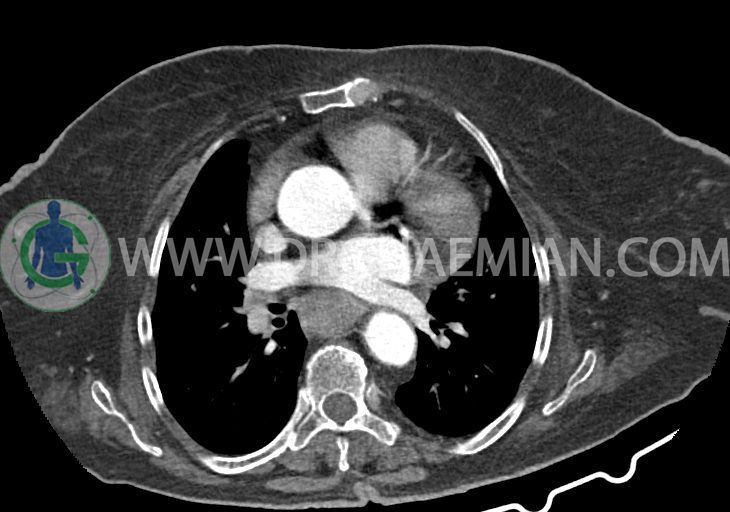

در سی تی اسکن اسپیرال ریه و مدیاستن – شکم و لگن با و بدون کنتراست خوراکی و وریدی (مولتی دیدکتور 16 با مقاطع ظریف و بازسازی های ساژیتال و کرونال):

تراشه و برونش های اصلی نرمال اند. پنومونی، پلورال افیوژن، جابجایی محتویات مدیاستن ، فیبروز ریوی و Collection مشهود نیست.

–کاردیومگالی همراه با pericardial effusion خفیف

–لنف نودهای non significant مدیاستینال با حداکثر SAD=6mm در فضای پره کارینا

–تغییرات دژنراتیو مهره های توراسیک و اسکولیوز توراکولومبار